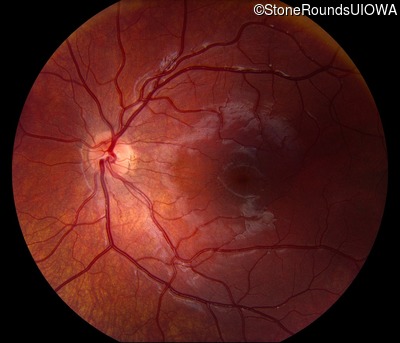

This 6 year old boy first experienced difficulty reading and seeing the blackboard at age 5.

| Age at visit: 6 years |

| Age at visit: 11 years |

| Age at visit: 14 years |

| Age at visit: 14 years (Visit 2) |